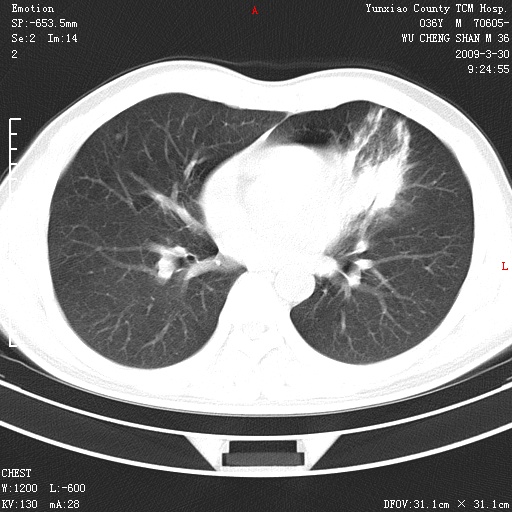

本院家属,胸痛,无咳嗽咳痰发烧病史,治疗一个月后病灶无明显改变,支气管镜示左肺慢性炎症,未见癌细胞,

胸痛,无咳嗽咳痰发烧病史,治疗一个月后病灶无明显改变,支气管镜示左肺慢性炎症,未见癌细胞,左肺下叶前段片状影,边缘不清,内见空支气管征,纵隔未见淋巴结肿大,周围无卫星灶,应考虑为炎性病变。

胸痛,无咳嗽咳痰发烧病史,治疗一个月后病灶无明显改变,支气管镜示左肺慢性炎症,未见癌细胞,左肺舌叶片状影,边缘不清,内见空支气管征,周围无卫星灶,应考虑为炎性病变。

左肺舌叶片状影,边缘不清,内见空支气管征,炎性病变